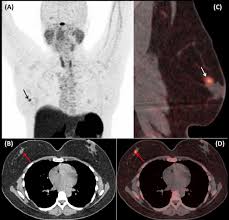

Pet/ct scans work well for breast, lung, colon and other. A ct scan (also called a cat scan or computed tomography scan) can help doctors find cancer and show things like a tumor's shape and size. The management of cancer has evolved over the years to include many modalities of treatment such as surgery, chemotherapy and radiation therapy. This test may reveal whether breast cancer has spread to the bone. A computed tomography (ct or cat) scan allows doctors to see inside your body. Positron emission tomography (pet) scans detect early signs of cancer, heart disease and brain disorders. Pet/ct scans provide significantly more information than ct scans, and are far more reliable when diagnosing cancer. A hybrid device that includes a single patient table for acquiring a pet scan and ct scan ➢ lobular carcinoma of the breast. The pet scanner detects signals that are given off from the tracer. Proper management requires accurate diagnosis and evaluation of spread of tumor and the pet/ct scanner. Pet scans, short for positron emission tomography, can detect areas of cancer by obtaining images of the body's cells as they work. Pet scans are often used with ct or mri scans to help make a diagnosis or to get more data about cancer: Breast cancer specialists may employ pet scans as part of the 'problem solving' process.

A computed tomography (ct or cat) scan allows doctors to see inside your body. This provides a series of images from many different angles. It gives detailed information about your cancer. 25.8) with a history of breast cancer and merkel cell cancer of the chin. Each has its own strengths.

Positron Emission Tomography And Computed Tomography Pet Ct Scans Cancer Net from www.cancer.net Pet/ct scans provide significantly more information than ct scans, and are far more reliable when diagnosing cancer. 25.8) with a history of breast cancer and merkel cell cancer of the chin. Each has its own strengths. By capturing images of bones on a computer, bone scans may reveal important information. Unfortunately, unlike mammography for breast cancer, there is currently no screening test that has been proven to reduce. Ct scans can detect cancer at a very small size. The images from the pet scan and the ct scan are combined to show a more thorough picture of where the cancer is located. It usually takes between 30 and 60 minutes.

Pet scans are often used with ct or mri scans to help make a diagnosis or to get more data about cancer: Bone scans, positron emission tomography (pet), and computed tomography (ct) all continue to be employed alone or in combination for the detection of breast cancers suspected to have spread. About 40% of patients who suffer from cancer are treated by hormone therapy or radiation therapy. Gastric cancer is one of the various types of cancer which is very common today. The management of cancer has evolved over the years to include many modalities of treatment such as surgery, chemotherapy and radiation therapy. Find out how you have it. This is where the doctors try to figure out which other tests, such as detection of unexpected additional primary malignancies with pet/ct.j nucl med. Each has its own strengths. Prostate pet/ct scans can detect cancer earlier than either ct scans alone or mri scans. In some cases, physicians use all three imaging techniques. One example is a combined pet and ct scan (known as pet/ct), available in some centers. This provides a series of images from many different angles. Positron emission tomography (pet) scans detect early signs of cancer, heart disease and brain disorders.